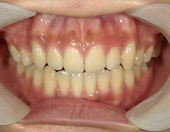

━━ 当院で働いている池谷彩乃さんが、前突および開咬を舌側ワイヤー矯正で治療しました。

中学生になり第二大臼歯が生えてから、真ん中の前歯2本が出てきて、八重歯も目立つようになりました。はじめは八重歯がチャームポイントだと捉えて気にしていませんでしたが、年々歯並びが悪化している気がしました。そのうち前突が原因で口が閉じづらく、寝ている時は口呼吸になってしまいました。

2年を少し過ぎたころには歯並びが良くなり、開咬もだいぶ改善されました。結婚式を予定していたため早期終了をさせていただきましたが、開咬が治ってハンバーガーをガブッと噛みきることができるようになって、とっても嬉しいです。式でもきれいな歯並びで、思いっきり笑うことができました。